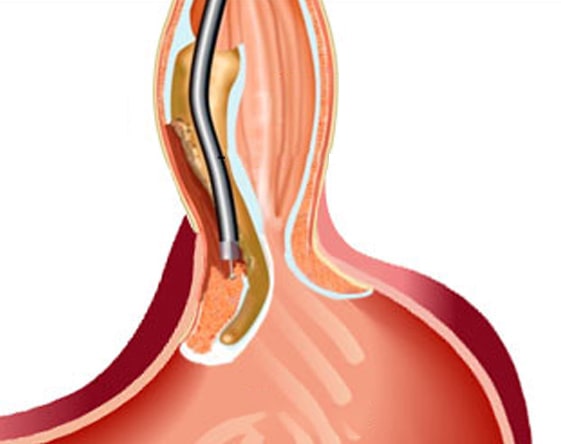

Balloon Enteroscopy

Endoscopy of the small bowel. The balloon-assisted enteroscopy is an incision-less....